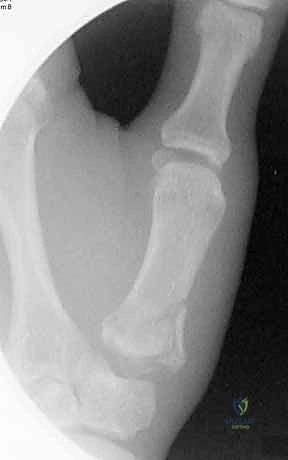

1. كسر بينيت (Bennett's Fracture)

هو أشهر أنواع كسور قاعدة الإبهام وأكثرها تعقيداً. وهو كسر داخل المفصل يتميز بوجود خط كسر مائل يفصل شظية صغيرة من الجانب الراحي الزندي (Volar-Ulnar) لقاعدة المشط الأول.

* الديناميكا المرضية: المشكلة الكبرى في كسر بينيت هي "القوى العضلية المعاكسة". بينما تظل الشظية الصغيرة ثابتة في مكانها بفضل رباط المنقار القوي، تقوم عضلة "مبعدة الإبهام الطويلة" (Abductor Pollicis Longus - APL) بسحب الجزء الأكبر المتبقي من عظم المشط إلى الأعلى والخلف، مما يؤدي إلى خلع جزئي (Subluxation) للمفصل.

* هذا الكسر غير مستقر بطبيعته ويحتاج دائماً إلى تدخل لتثبيته.

2. التصوير بالأشعة السينية (X-rays)

هي الأداة التشخيصية الأولى والأهم. يتم إجراء صور أشعة بزوايا محددة جداً:

* المنظور الأمامي الخلفي (AP View).

* المنظور الجانبي الحقيقي (True Lateral View): وهو ضروري جداً لتقييم مدى الخلع أو الانزياح في المفصل.

* منظور روبرت (Robert's View): وضعية خاصة للأشعة السينية تظهر مفصل الإبهام الرسغي السنعي بوضوح تام وتكشف عن أدق التفاصيل في كسور بينيت ورولاندو.